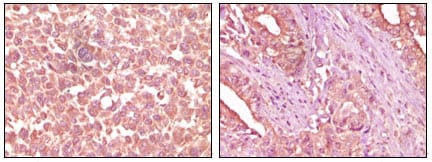

分类: 科研抗体货号: 20088别名: K1; CK1; EHK; EHK1; EPPK; KRT1A; NEPPK应用: IHC反应种属: Human

分类: 科研抗体货号: 20069别名: APP应用: IHC反应种属: Human